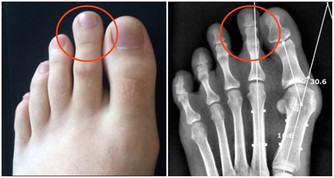

從前得痛風、脂肪肝的大多是中老年人,這兩年越來越多二三十歲的年輕人,竟然也得上這些病了。